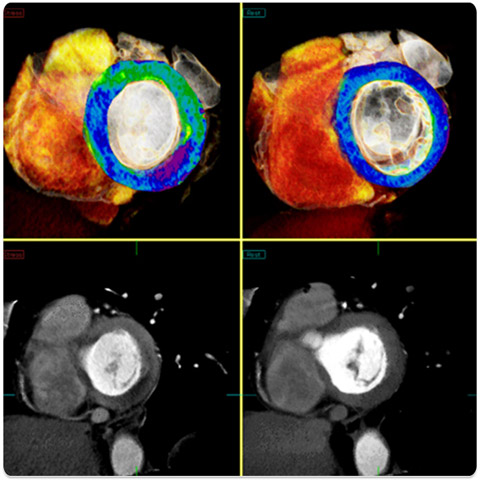

Koronar CTA mit AQUILION ONE™ - genaueste Herz- und Arterien-Aufnahmen

Unser neues CT AQUILION ONE™ / GENESIS EDITION ermöglicht die exakte Diagnose von Läsionen (Verletzung oder Störung der Funktion eines Organs oder Körperglieds), die mit herkömmlicher statischer Bildgebung nicht zu sehen sind. Insbesondere können Probleme des Herzens und der Herzarterien beim sogenannten Koronar-CTA (CT-Angiographie) sichtbar gemacht werden.

- Die Darstellung des ganzen Herzens in einem einzigen zeitlich uniformen Volumen

- Genaue Diagnose: Das Koronar-CTA ermöglicht eine genaue Beurteilung der Gewebedurchblutung des Herzmuskels. Zudem kann präzise ermittelt werden, ob eine mangelnde Versorgung von Koronararterien vorliegt.

- Ultrageringe Dosis: Alle erforderlichen Perfusionsdaten können mit nur einem Scan erfasst werden.

Der Aquilion ONE führt Koronarangiographie mit einer prospektiv ausgelösten Spiraltechnik durch. Dadurch wird die Gleichmäßigkeit in Richtung der Z-Achse im Vergleich zu Verfahren mit schrittweisen Aufnahmen gewährleistet.